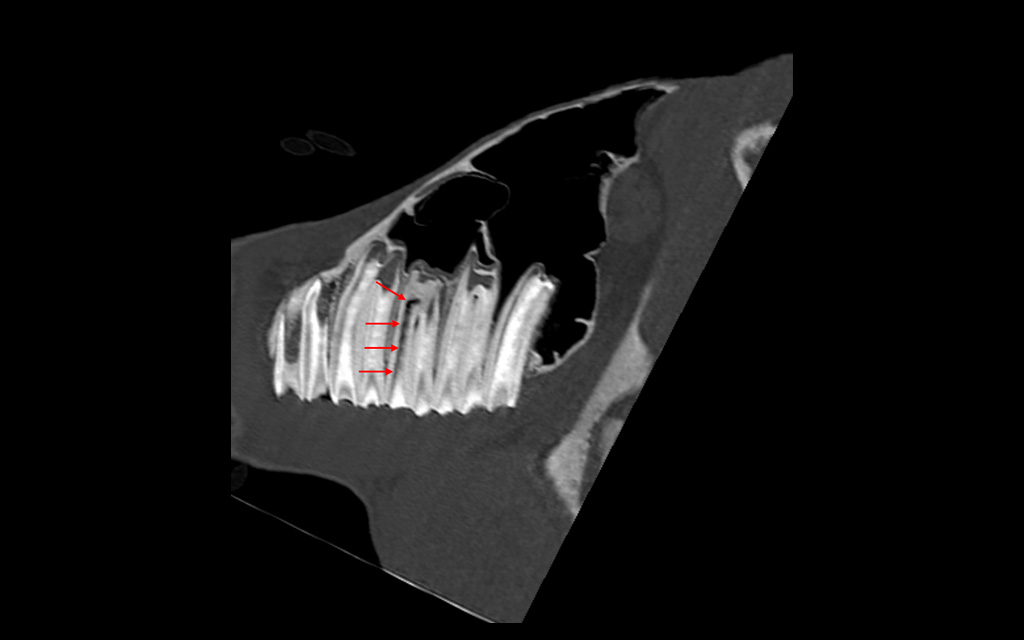

Warmblood yearling presented with an injury at the left tarsal joint. (Bone Window, Sagittal Plane)

Bone window, frontal: new bone formation and lytic lesions in talus and central tarsal bone

Bone window, transverse: new bone formation and lytic lesions in talus and central tarsal bone

Massive traumatic bone lesions in the left talocrural joint with lytic lesion in the adjacent joint surfaces.

In addition, however, there is severe desmopathy and enthesopathy of the medial collateral ligament. The CT images show severe longitudinal tears and fibrillations in both the long and short parts of this ligament. The short part (pars tibiocalcanea) is partially ruptured.